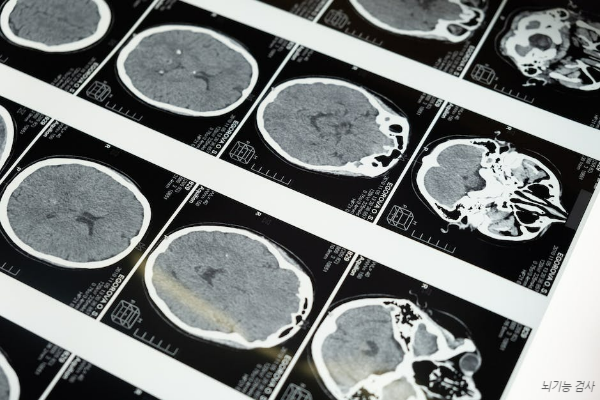

모르면 최악상황 뇌혈관 질환 전조증상과 긴급대처법

우리 뇌는 다른 신체기관과 유사하게 혈액을 공급받으면서 기능을 합니다. 만약 정상적인 혈액공급이 안 된다면 뇌기능에 문제가 생기는데, 이게 바로 뇌혈관질환이라고 합니다. 만약 단 몇 분의 짧은 시간에라도 혈관이 막히거나 내부 출현이 발생하는 뇌혈관 질환은 뇌세포가 파괴되고 치명적인 상해를 입을 수 있습니다. 뇌는 우리 심장에서 공급하는 혈액의 20% 정도를 순환시켜야 할 정도로 많은 양의 혈액순환으로 기능하는 곳이므로 간혹 고산지대로 올라가서 겪게 되는 저산소증도 뇌기능에 영향을 주게 됩니다. 이러한 혈액 공급에 문제가 생겨서 발생하는 뇌혈관 질환에는 대표적으로 뇌출혈, 뇌경색, 뇌동맥류, 지주막출혈 등이 있어요. 흔히 의학계에서 뇌졸중이라고 부르고, 흔히 중풍이라고 불리는 질환입니다. 여기서 뇌혈관이 ..